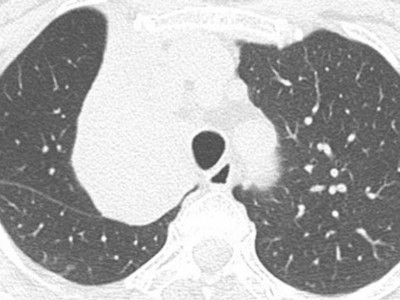

Bildnachweise